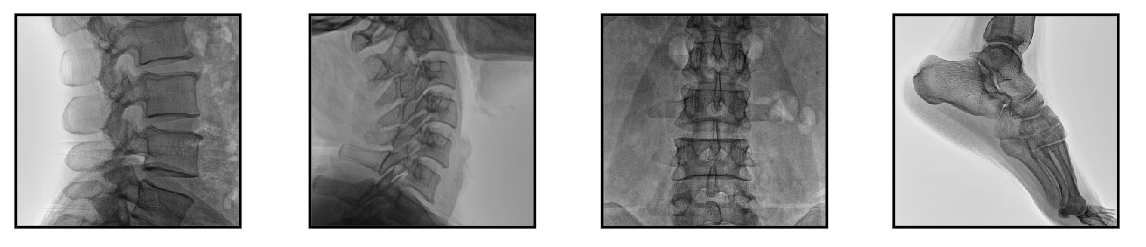

移動式C臂機可以直接應用于骨科手術中的術中定位,診斷檢查整骨、復位、打釘?shù)鹊男Ч?,以及配合各種微創(chuàng)手術的開展、取出體內(nèi)金屬異物等治療中發(fā)揮了獨特的作用,是諸多醫(yī)院放射科設備的選擇。

隨著移動式C臂機在外科手術中應用不斷增加,醫(yī)護人員暴露在射線輻射中的機會不斷增大,如何做好移動式C臂機透視防護是骨科醫(yī)生都關心的問題。以下是小編給大家總結(jié)的幾點。

普愛醫(yī)療移動式C臂機,應用先進技術,檢測圖像清晰,一目了然,輻射量低,安全,可信賴。